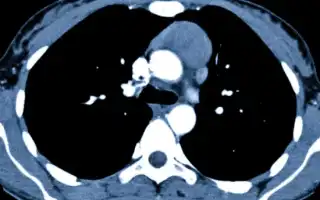

Если у пациента подозревают наличие кист перикарда, врач назначает целый комплекс инструментальных исследований:

- КТ – инструментальный диагностический метод, который даёт возможность хирургу увидеть все контуры кист. Также можно понять, каким образом они расположены, а также каковы их особенности.